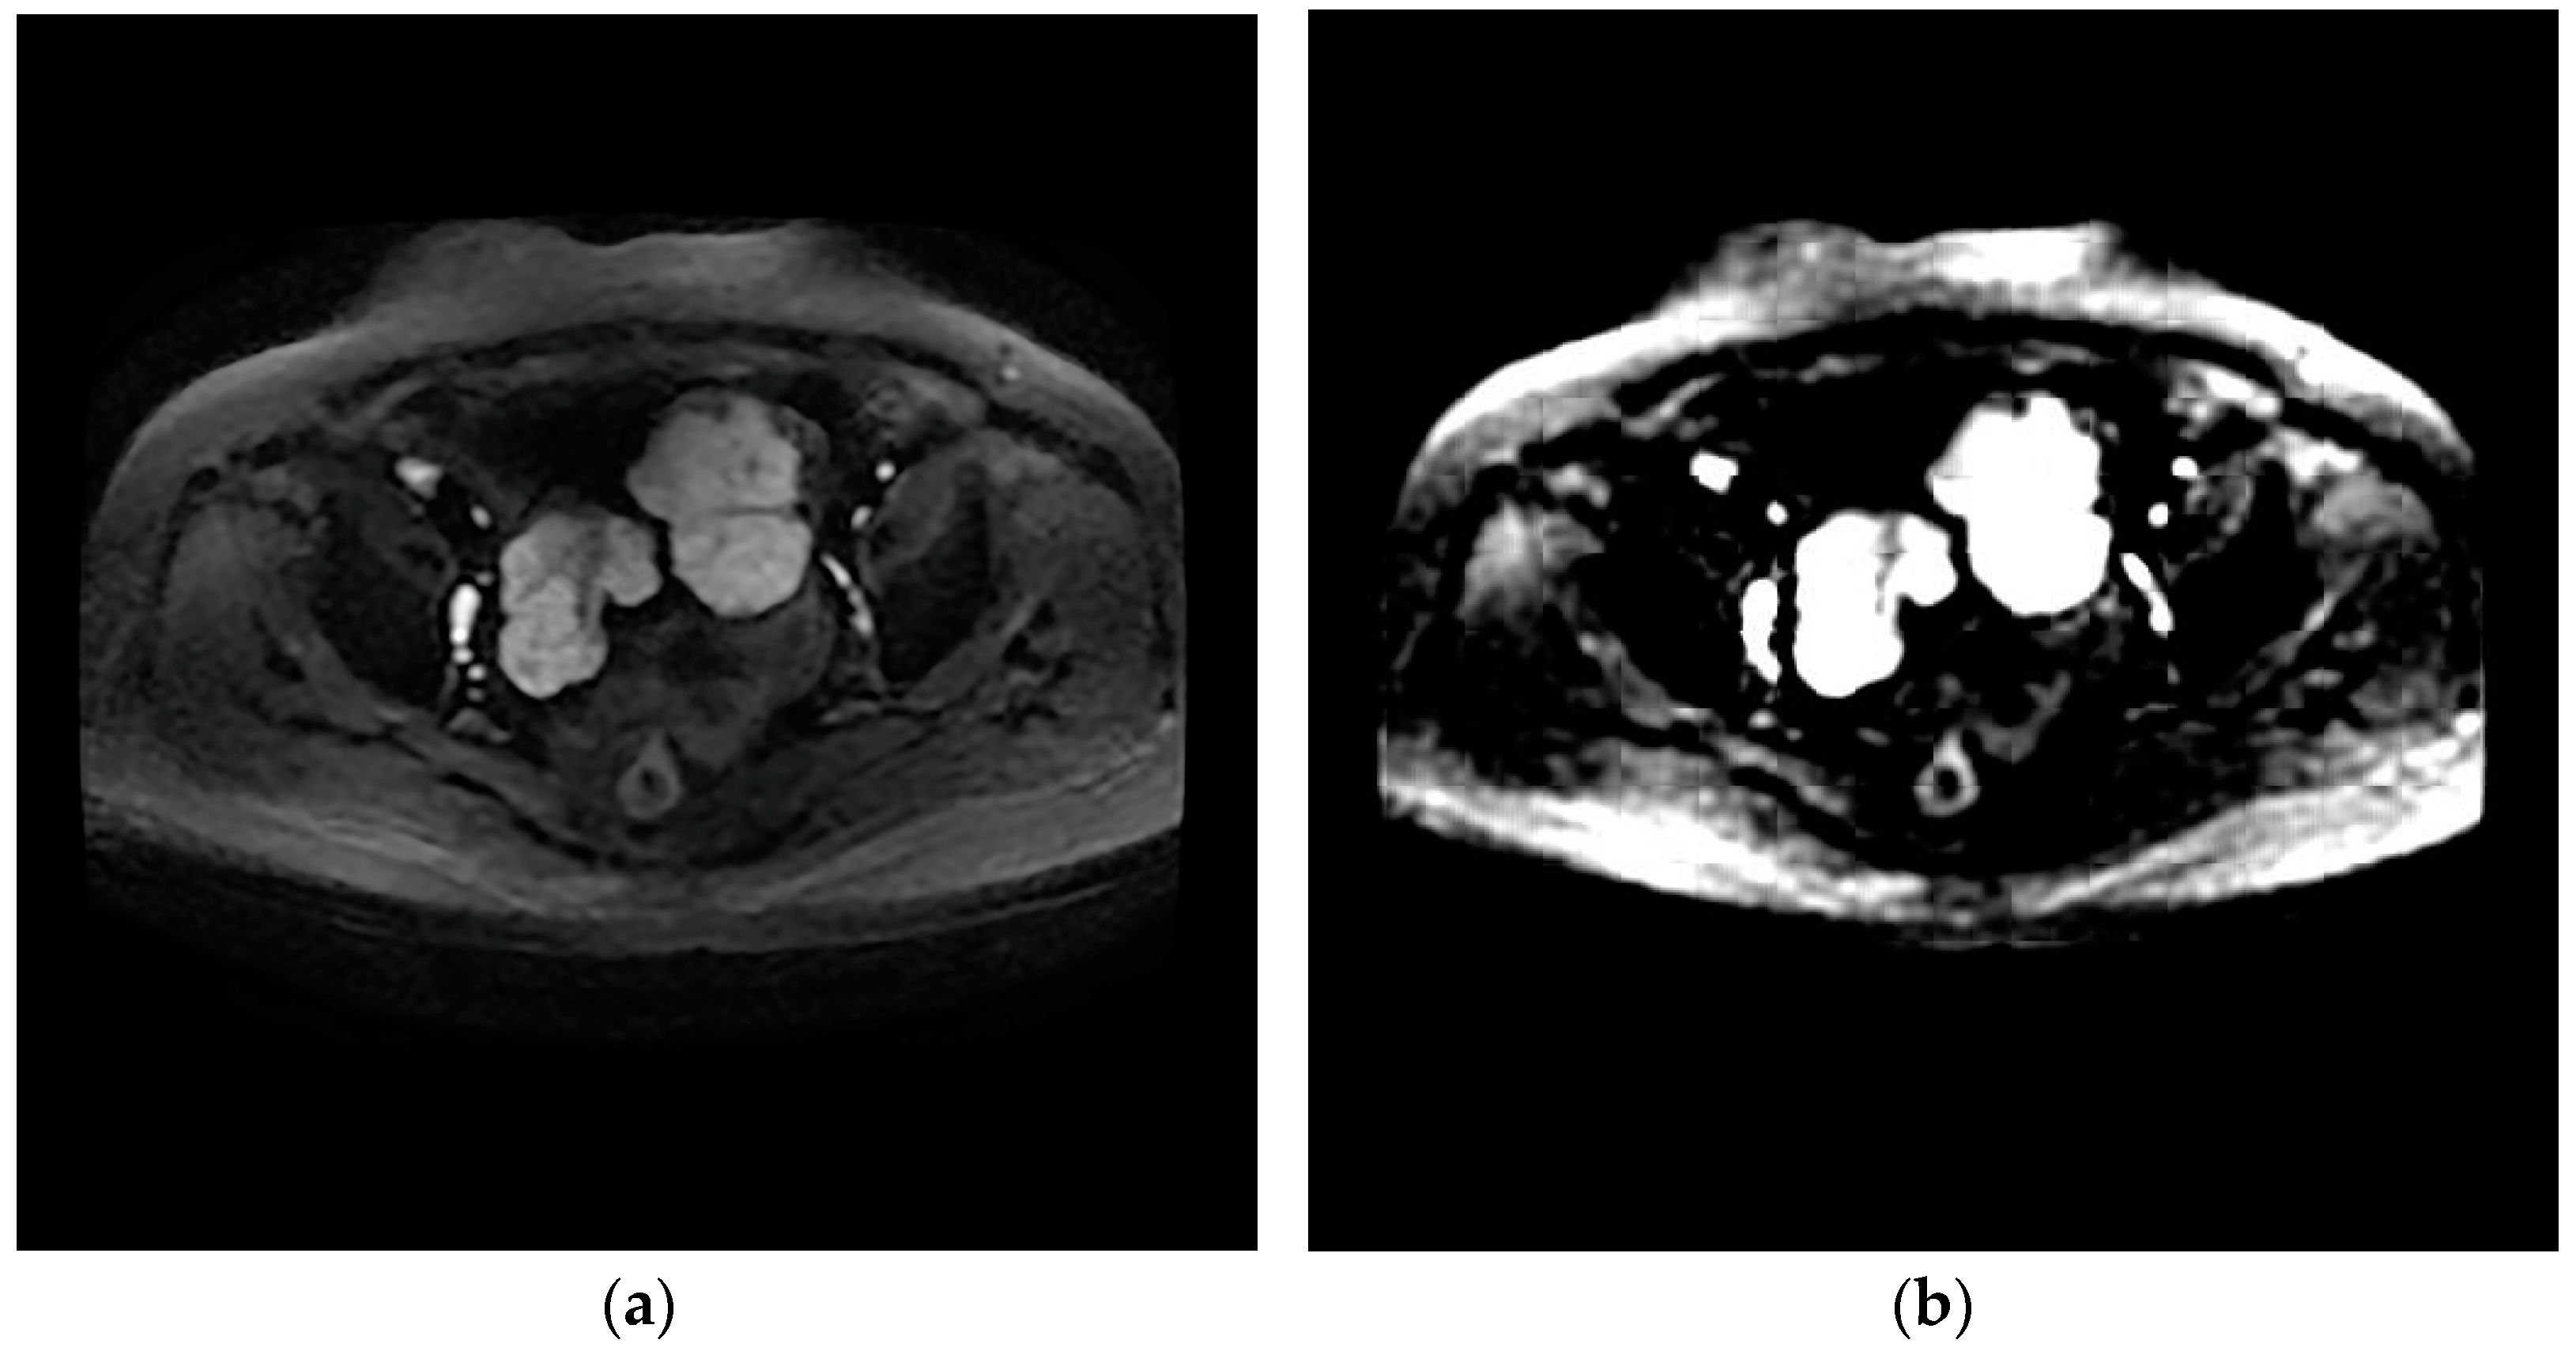

The design of the network can provide the value of image features. The network eliminates redundant information through learners and decoders, and only retains features that can reflect the inherent characteristics of HGSOC, and therefore a small number of features can contain most of the information of tumor images. Therefore, we input T2WI and DWI images from the same patient into the network and reconstructed them into images. It was found that the reconstructed images based on the features were similar to the original images, which proves that the internal features of the images are learned, as shown in Figure 3 and Figure 4.

Figure 3.

Axial T2-weighted image (a); generated image (b).

Figure 4.

Axial DWI image (a); generated image (b).